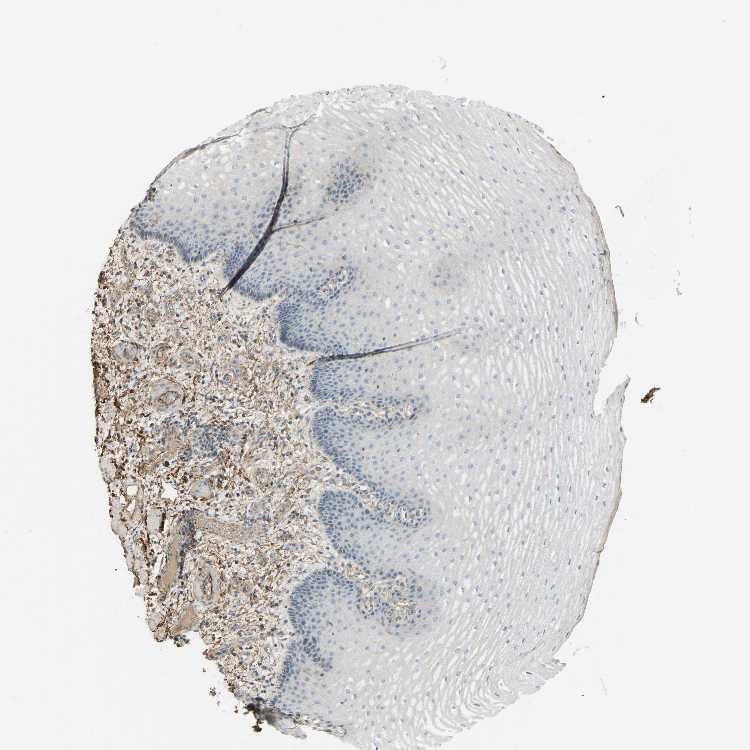

ESOPHAGUS - Antibody stainingi

Antibody staining in the annotated cell types in the current human tissue is reported as not detected, low, medium, or high, based on conventional immunohistochemistry profiling in selected tissues. This score is based on the combination of the staining intensity and fraction of stained cells.

Each image is clickable and will lead to virtual microscopy that enables deeper exploration of all samples and also displays staining intensity scores, fraction scores and subcellular localization as well as patient and tissue information for each sample.

Antibody HPA001934Antibody CAB018622

Squamous epithelial cells Not detectedNot detected